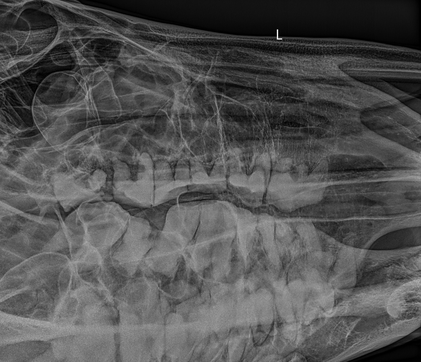

Röntgendiagnostik

Für eine präzise Diagnostik setzen wir auf modernste digitale Röntgentechnik zur Erkennung von:

• Zahnwurzelveränderungen der Backenzähne

• Schneidezahnerkrankungen (z.B. EOTRH)

• Kieferhöhlenerkrankungen

• Kiefergelenkserkrankungen

• Kieferfrakturen/-tumoren